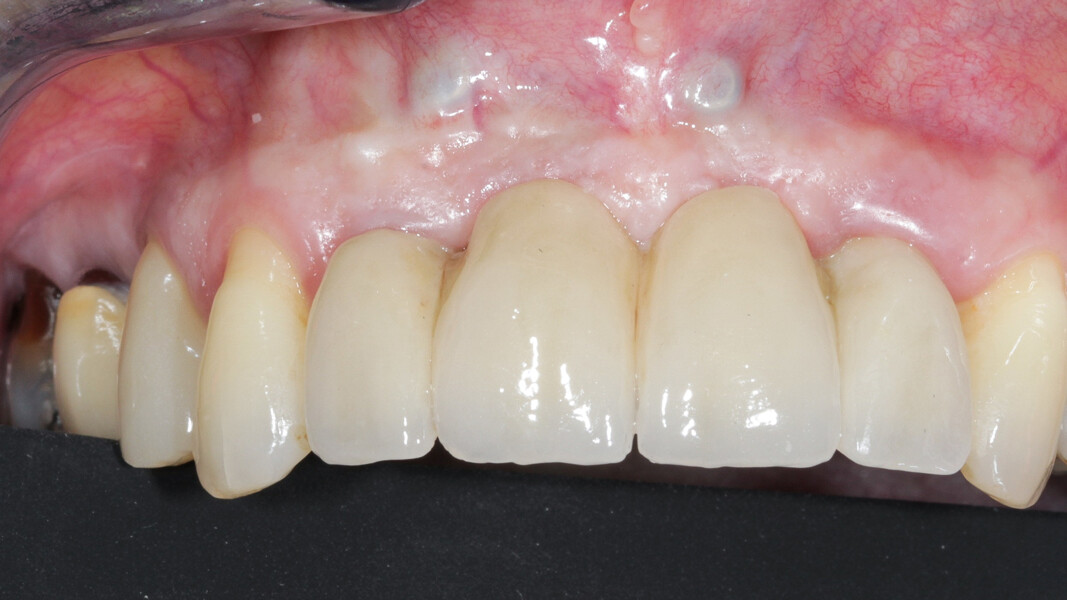

Une patiente de 49 ans nous a été adressée par l’un de nos confrères pour le remplacement de ses quatre incisives maxillaires (Fig. 23). Dans un contexte parodontal avancé, ses incisives centrales présentent une mobilité terminale (classe IV) elle n’ose plus les brosser de peur de les perdre lors de la manoeuvre. La patiente ne présente pas de problèmes de santé particuliers.

À l’examen, on observe une mobilité des quatre incisives maxillaires, une insuffisance osseuse verticale et horizontale, associées notamment au niveau de 11 et 21, la présence de plaque, de tartre et d’inflammation gingivale, surtout au niveau du bloc antérieur maxillaire. On note également la présence d’une dent de sagesse (dent 18) perdue (Figs. 24–26).